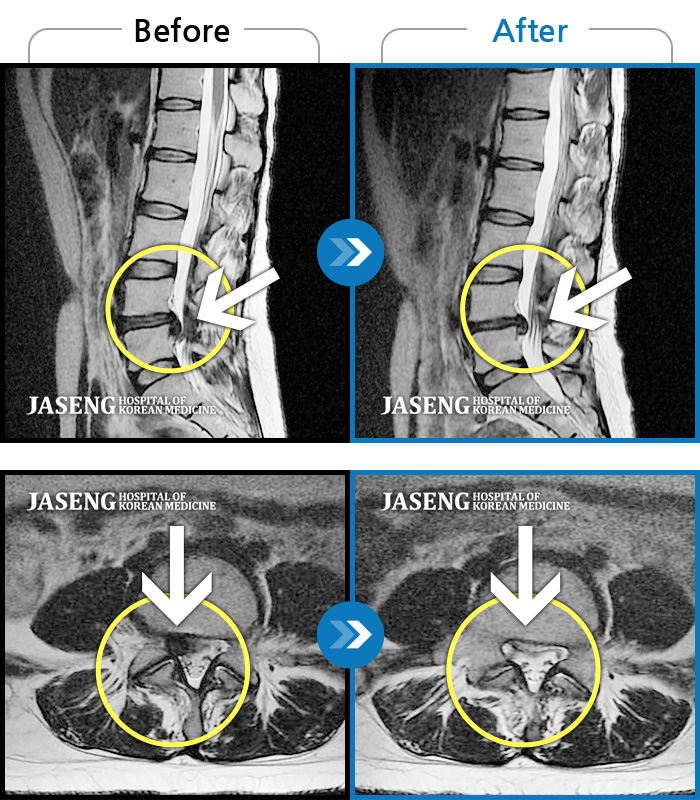

MRI 치료사례

심한 허리 통증과 우측 다리 통증